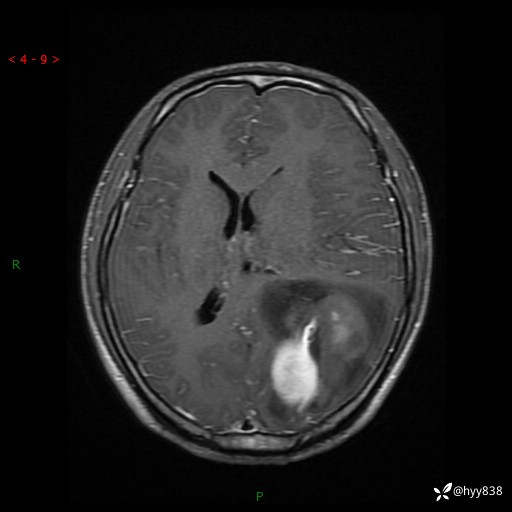

病例年轻小伙,头痛伴呕吐半年,渐进性加重1月。疑难病例,第一次见--结果公布~

性别:男

年龄:21岁

简要病史:头痛伴呕吐半年,渐进性加重1月

颅脑MRI平扫+增强